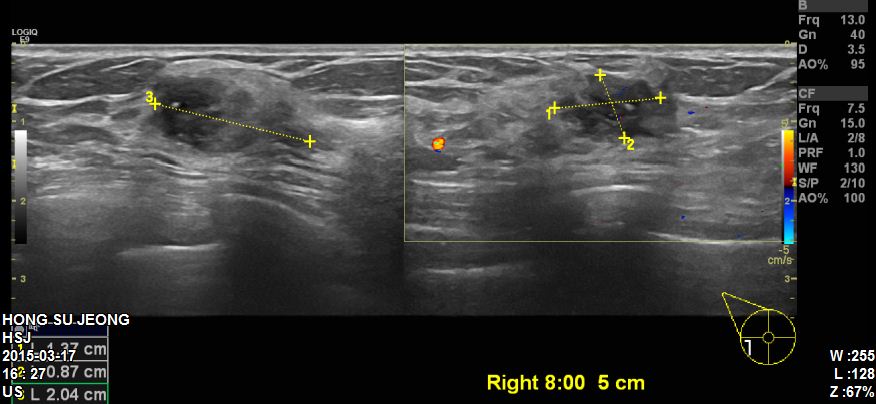

본원에 내원하신 60대 환자분이십니다

유방초음파 시행후 좌측유방에 8 : 00방향에 2.04cm의 혹을 조직검사 시행하였고

결과상 침윤성유관암 진단되었습니다.